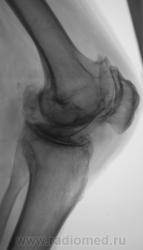

Боли в коленном суставе.

Деформирующий гонартроз 4 ст. или есть какой-то подвох? Двойной контур суставной поверхности медиального мыщелка бедра не Кениг ли случайно?

Не совсем точно выразиласьУлыбаюсь, не подвох, а что-то неординарное и заковыристое, например, манифестный ДОА в сочетании с чем-нибудь редко встречающимся.

я бы по коссинской 2-3 ст. деформирующего артроза написала, ито 3 ст это когда уже совсем не прослеживается суставной щели, а здесь она есть.

Согласен с DR.RAD двухсоронний гонартроз 2-3степени.

При второй стадии по классификации Н.С. Косинской, суставная щель-то должна быть сужена более чем на 50 %?

да а 3 стадия 2/3 как в данном случае...

Мне показалось, что суставная щель вовсе и не так уж сужена.А вот в пателло-феморальный суставе резкое сужение суставной щели.Выраженный субхондральный склероз, краевые остеофиты суставных поверхностей костей.А что там у Косинской по этому поводу написано, помните?

Н.С. Косинская - уже в прошлом (с уважением)... Понятно, что здесь первоочередным критерием являются деформирующие (обезображивающие)

остеофиты, а не ширина суставной щели; и суставные концы костей уплощены ("просели" за счёт остеопороза), и м/мыщелковые бугорки сглажены (бывшие остеофиты).

Оцениваем же в комплексе - все изменения.